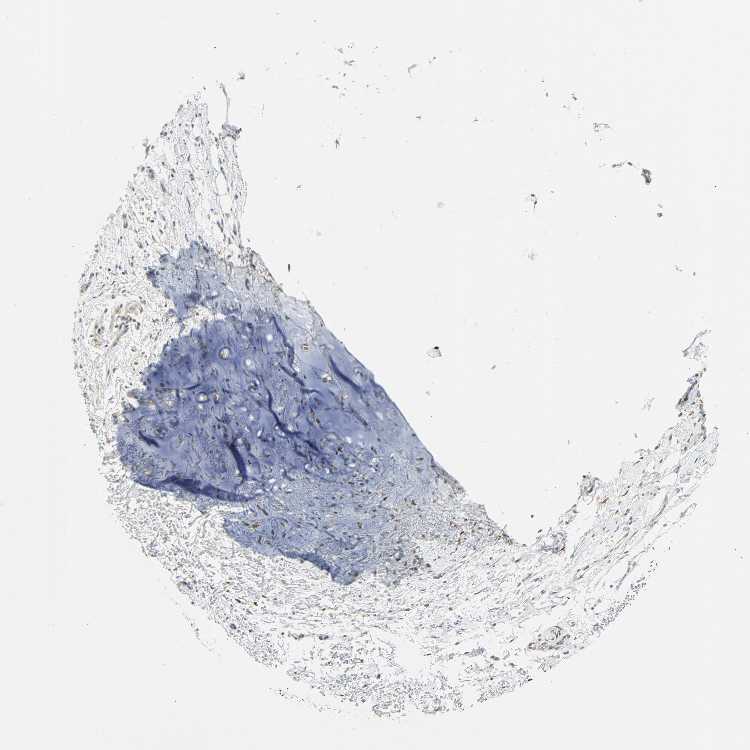

SOFT TISSUE 1 - Antibody stainingi

Antibody staining in the annotated cell types in the current human tissue is reported as not detected, low, medium, or high, based on conventional immunohistochemistry profiling in selected tissues. This score is based on the combination of the staining intensity and fraction of stained cells.

Each image is clickable and will lead to virtual microscopy that enables deeper exploration of all samples and also displays staining intensity scores, fraction scores and subcellular localization as well as patient and tissue information for each sample.

Antibody HPA015794Antibody CAB004544

Chondrocytes -Not detected

Fibroblasts LowLow

Peripheral nerve Not detectedLow